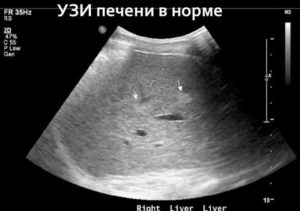

Эхоанатомия органа

Во время проведения УЗИ печенка визуализируется в правом верхнем квадранте живота. В большинстве случае можно определить все четыре ее анатомические доли: правая и левая, квадрантная и хвостатая. С помощью УЗИ также изучают восемь сегментов печени.

Величину органа оценивают на основании определения максимального косого размера правой части по среднеключичной линии (не более 150 мм), толщина, или передне-задний размер, левой (до 60 мм).

Капсула печени четко определяется как гиперэхогенная структура вокруг ее контура, который должен быть ровным и непрерывным.

Неизмененная паренхима печени на УЗИ выглядит мелкозернистой и гомогенной. Ее эхогенность по сравнению с правой почкой немного выше, но ниже, чем у поджелудочной железы.

Анэхогенные трубчатые образования, которые визуализируются на фоне гомогенной эхоструктуре печени, соответствуют веткам воротной и печеночным венам. Их различают на основе анатомического расположения и определения эхогенных стенок в ветках воротной вены.